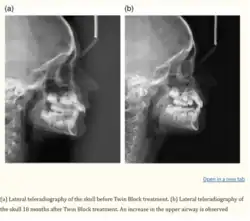

Figure 9: Cephalometric changes: pre-treatment (black lines), pre-debond (red lines)[22]

With the help of CBCT which produces detailed 3D images, the skeletal effects of the condyle (the curved part of the mandible which fits into the TMJ) was recorded.[23]

The size of the condyle, distance between the two condyles, and the length of the mandible increased. The twin block appliance enabled the growth of the condyle in a backwards and upwards direction. Based on cephalometric analysis, as given in Figure 21, the angle of SNB (the position of the mandible to the base of the skull) increased, and the angle of SNA (the position of the maxilla to the base of the skull) and ANB (anteroposterior relationship between the maxilla and mandible) decreased thus reducing the Class II skeletal malocclusion.[24]

Singh et al. found that the Twin Block appliance can improve airway function by increasing the posterior airway space. This advancement in the mandible can be particularly beneficial for patients suffering from obstructive sleep apnea (OSA) or other breathing difficulties, as it helps to reduce airway obstruction during sleep. This makes the appliance useful not only for orthodontic correction but also for improving overall health and breathing.[25]